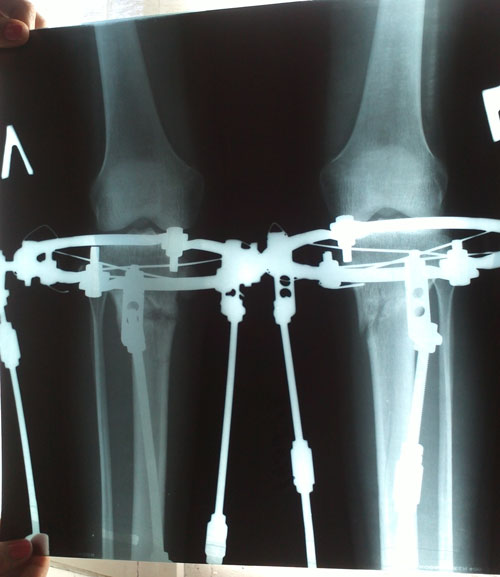

- Хирург: Онипко Н.Н.

- Диагноз: о-образная деформация нижних конечностей

- Дата операции.: 12.03.2013

38 дней с момента операции.

Ножки в норме, продолжаем фиксацию!

Дата операции 15.03.2013г.

Дата снятия аппаратов 17.05.2013г.

Срок лечения 62 дня.